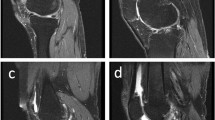

Figure 6 displays ultrasound images (A–E) of five patients with varying pathological conditions, with green rectangular boxes identifying the target regions. These images highlight the distribution of blood flow across different anatomical sites and their pathological features. Grading was performed based on blood flow signal density, synovial characteristics, joint effusion, and the severity of soft tissue lesions, revealing a progressive trend from mild to severe (A as grade 0, B as grade 1, C as grade 2, and D and E as grade 3).

Blood Flow Signal Grading in Patients with Different Pathological Conditions (A) Ultrasound image of a patient graded as SMI level 0; (B) Ultrasound image of a patient graded as SMI level 1; (C) Ultrasound image of a patient graded as SMI level 2; (D and E) Ultrasound images of patients graded as SMI level 3.

Figure 6A illustrates effusion within the suprapatellar bursa and medial and lateral joint spaces of the left knee (measuring 2.33 × 0.48 cm, 1.66 × 0.38 cm, and 1.36 × 0.38 cm, respectively). Synovial thickening and reduced echogenicity suggest mild inflammatory changes in the synovium. The absence of significant blood flow signals indicates minimal vascular proliferation and mild osteoarthritis. Furthermore, thickening of the lateral collateral ligament with blurred fibrous structures suggests potential ligament injury. This case is classified as grade 0.

Figure 6B reveals effusion within the suprapatellar bursa (0.61 × 0.17 cm) and medial (0.84 × 0.30 cm) and lateral (0.58 × 0.34 cm) joint spaces of the left knee, along with synovial thickening and heterogeneous echogenicity, indicative of inflammatory changes. The presence of minimal blood flow signals suggests early active inflammation, with a noticeable increase in vascular activity compared to Fig. 6A. This case is assigned a grade of 1.

Figure 6C shows a hypoechoic region at the proximal attachment of the right gastrocnemius muscle, accompanied by a substantial presence of blood flow signals, indicative of localized strain. Blurred fibrous structures suggest mechanical damage coupled with localized inflammatory responses. The pronounced increase in blood flow signals reflects heightened dynamic inflammatory activity. Despite the localized nature of the lesion, the significant enhancement of blood flow signals justifies a grade of 2.

Figure 6D depicts effusion in the joint cavity and medial and lateral joint spaces of the left knee (0.98 × 0.23 cm, 0.81 × 0.38 cm, and 2.86 × 0.59 cm, respectively). Marked synovial thickening and reduced echogenicity are evident, indicative of osteoarthritic inflammatory changes. Edema in the soft tissue beneath the patellar edge, coupled with abundant and blurred blood flow signals, suggests notable alterations in synovial and soft tissue vascular supply. The extensive nature of the lesion and the active inflammatory response are consistent with a grade of 3.

Figure 6E demonstrates thickening and hypoechoic areas (3.03 × 0.88 cm) in the prepatellar fat layer of the right knee, accompanied by abundant blood flow signals. Effusion is observed in the suprapatellar bursa and medial and lateral joint spaces (1.76 × 0.32 cm, 1.23 × 0.28 cm, and 0.74 × 0.28 cm, respectively). The dense distribution of blood flow signals indicates pronounced inflammatory changes in the synovium and soft tissues, as well as joint cavity effusion, showing activity levels comparable to those in Fig. 6D. This case is classified as grade 3.

Differences, similarities, and severity assessment

All cases depicted in Fig. 6 display osteoarthritic characteristics, including synovial thickening, reduced echogenicity, and joint effusion, with varying degrees of enhanced blood flow signals correlating to different levels of inflammatory activity. Soft tissue abnormalities are also evident, such as ligament thickening in Fig. 6A, strain in Fig. 6C, and edema beneath the patellar margin in Fig. 6D, underscoring the link between osteoarthritis and soft tissue lesions. The primary variations are observed in the distribution and density of blood flow signals: Grade 0 (Fig. 6A) exhibits no detectable blood flow signals, indicating minimal inflammatory response; Grade 1 (Fig. 6B) reveals sparse blood flow signals, signifying early active inflammation; Grade 2 (Fig. 6C) shows localized but abundant blood flow signals; and Grade 3 (Fig. 6D and E) demonstrates densely concentrated blood flow signals, reflecting extensive active inflammation. Progression from Fig. 6A to Fig. 6E reveals a marked escalation in lesion severity, with synovial thickening expanding from localized to widespread areas, blood flow signal density increasing significantly, and inflammatory activity intensifying from mild to severe. Grade 0 represents static synovial inflammation, Grades 1 and 2 indicate progressively active inflammatory states, and Grade 3 corresponds to the most advanced inflammatory phase, characterized by significant vascular proliferation and associated tissue changes. This grading system effectively illustrates the dynamic progression of osteoarthritis, providing a robust framework for quantifying blood flow and advancing automated grading methodologies based on the optical flow model. Additionally, as blood flow signal grades increase, the patterns of SMI Motion Density (SMI-MD) and SMI Elastic Density (SMI-ED) curves become more distinct and exhibit consistent trends, further validating the grading system’s reliability.